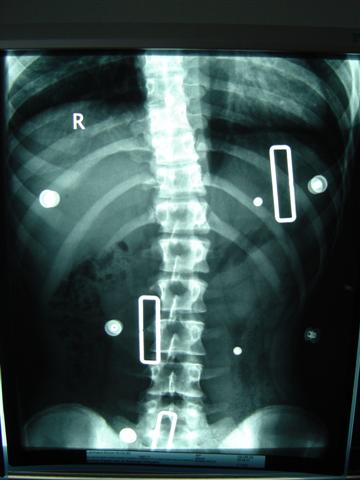

So und jetzt noch das Röbi im Nachtkorsett, leider ist die obere Krümmung nicht wirklich oben

ImNachtkorsett 1.JPG

ImNachtkorsett 1.JPG (25.2 KiB) 9662 mal betrachtet

Beide Korsette das CBW-Tageskorsett und das Charleston-bending-Nachtkorsett haben zu wenig Derotation!

Der Hauptkritikpunkt an Charleston ist übrigens die fehlende Derotation. Die WS ist nur im Röntgenbild im Liegen scheinbar gerade aber immer noch wie in deinem Fall fast auf NASH & MOE 3 verdreht (torsionsrotiert)